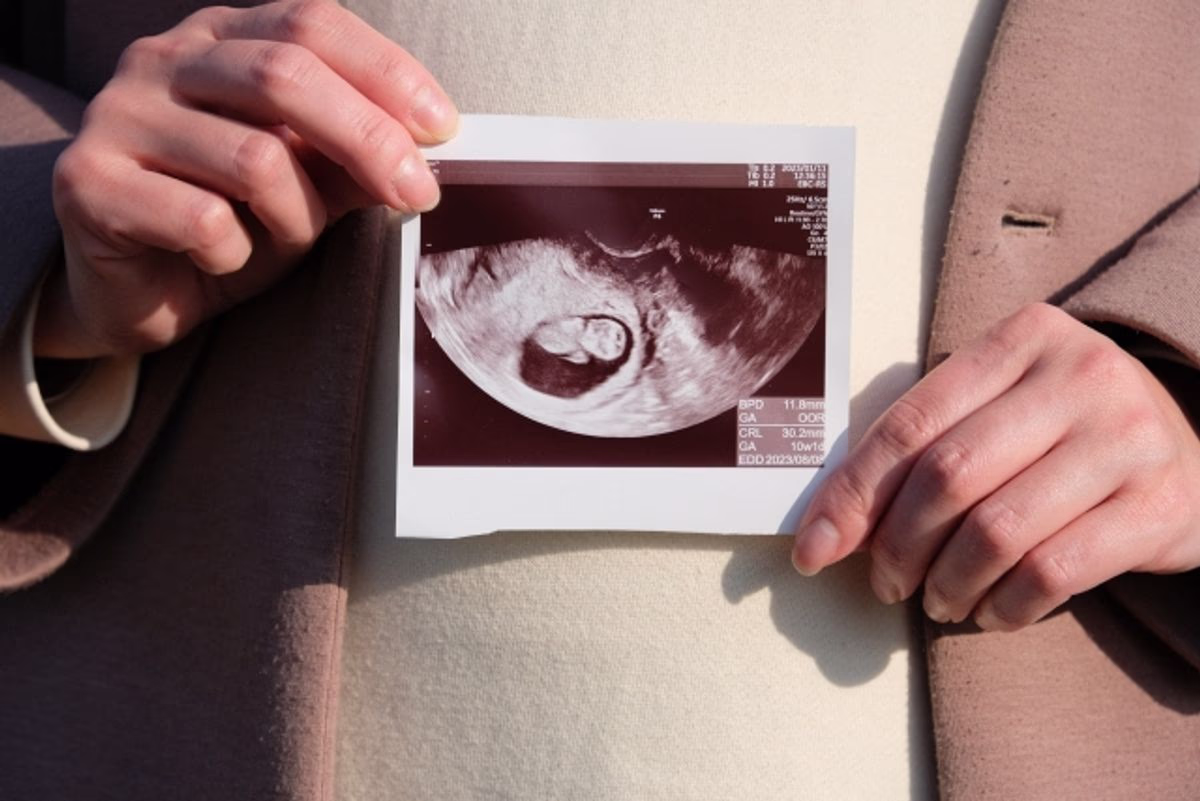

赤ちゃんの性別がわかるのは妊娠中期頃です。

一般的に、男の子は14〜15週頃、女の子は17〜18週頃にわかります。

どちらの場合も、20週前後になるとほとんど確定します。

一般的には、超音波検査(エコー)で赤ちゃんの性別を確認します。

超音波検査(エコー)で確認できる

超音波検査(エコー)では、赤ちゃんの外性器の形で性別を判定します。

超音波検査(エコー)の場合、医師が画像を見て判断するため、間違いが全くないとは言えません。

ただし、最近の医療機器は性能が上がっているため、性別判定を間違えることはほとんどないでしょう。